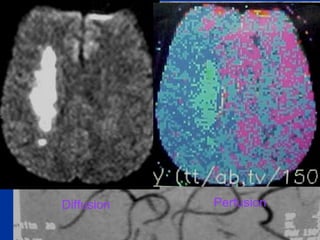

Diffusion Perfusion